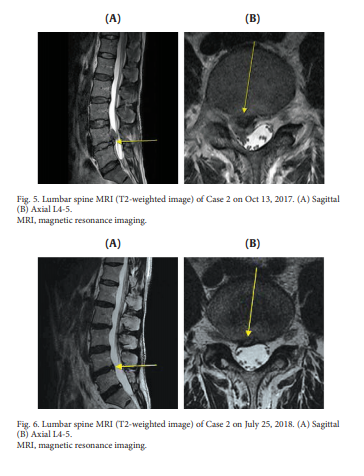

아래의 논문은 목허리 디스크에 도침치료는 경항통과 요통의 개선은 물론 MRI상에서 탈출한 수핵의 재흡수를 확인한 연구입니다

이 연구의 목적은 침도치료에 따른 허리디스크 탈출 수핵의 재흡수에 관한 보고였습니다.

두 명의 환자가 경추 또는 요추 추간판탈출증에 대한 통합적인 한약 치료를 포함하는 침도치료를 받았습니다. 자기공명영상(Magnetic Resonance Imaging)은 치료 전후의 영상을 생성하기 위해 사용되었고, 입원 및 퇴원 시 환자를 평가하는 데 사용되는 수치 등급 척도 점수 및 운동 범위를 체크하였습니다. 두 경우 모두 자기 공명 영상에서 각각의 허리 디스크의 상당한 재흡수가 관찰되었고, 수치 등급 척도 점수가 감소했습니다. 동작 범위가 1건에서 개선되었습니다. 이 연구는 침도 치료가 탈핵성 허리디스크의 디스크재흡수 및 통증 완화에 효과적인 치료법일 수 있다는 것을 보여줍니다.

*도침치료후 재흡수된 허리디스크, 침료치료효과는 놀랍습니다.